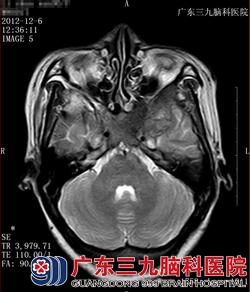

图三 图四

图三:T2WI:颅底骨质信号减低,左侧中颅窝病变呈不均低信号。

图四:T1WI:颅底骨质T1WI高信号消失,左侧中颅窝病变呈低信号。